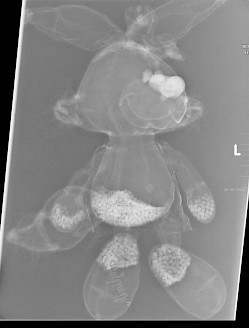

Wir einigten uns, dass auch Minihops Schmerzen habe, und so schlug ich ihr vor, doch zuerst mal ihren treuen Begleiter zu röntgen, damit sie sieht, dass da gar nichts schlimmes passiert. Nach etwas zögern rückte sie Minihops heraus und ich legte ihn immer noch unter skeptischer und ängstlicher Beobachtung des Mädchens auf eine Kassette unter die Röntgenröhre.

Dem Mädchen erklärte ich jeden Schritt den ich tat und ging mit ihr – immer noch an der Mutter klebend - zum Schaltpult, löste den Schuss aus, ging zum Auslesegerät und ließ die Kleine zuswehen, wie das Bild aufgebaut wurde. So langsam merkte ich wie sie langsam auftaute. Jedenfalls ließ das Geschluchze erheblich nach und der Klammergriff zur Mutter löste sich auch schon merklich. Wir besprachen das Bild von Minihops und stellten fest, dass das Kuscheltier keinerlei Brüche oder sonstige ernsthafte Erkrankungen habe!

Das Bild von Minihops habe ich ihr später an die eMail-Adresse der Mutter nach Hause geschickt!